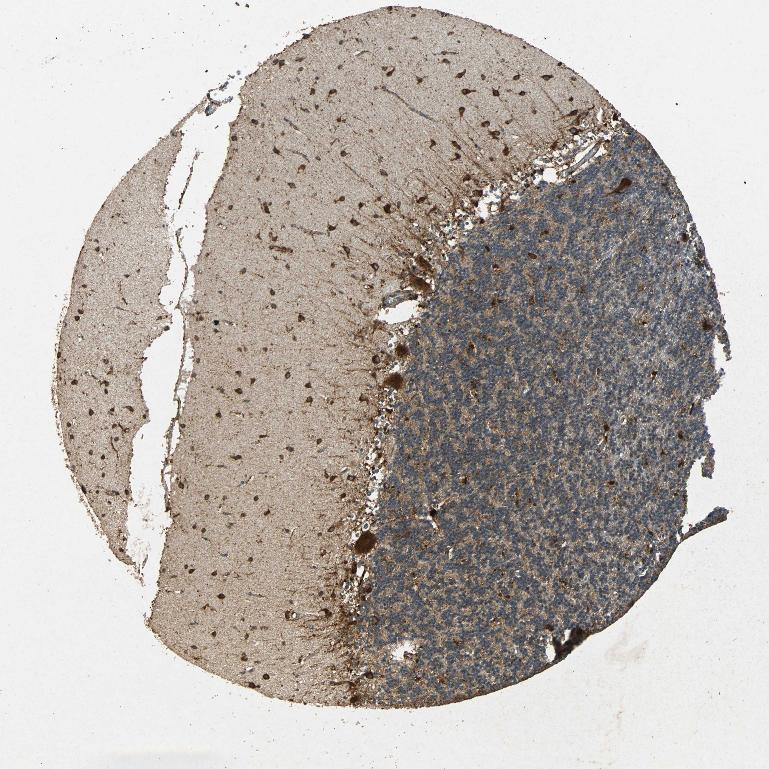

CEREBELLUM - Antibody stainingi

Antibody staining in the annotated cell types in the current human tissue is reported as not detected, low, medium, or high, based on conventional immunohistochemistry profiling in selected tissues. This score is based on the combination of the staining intensity and fraction of stained cells.

Each image is clickable and will lead to virtual microscopy that enables deeper exploration of all samples and also displays staining intensity scores, fraction scores and subcellular localization as well as patient and tissue information for each sample.

Antibody HPA030711Antibody CAB006269

Purkinje cells HighHigh

Cells in granular layer Not detectedMedium

Cells in molecular layer Not detectedHigh